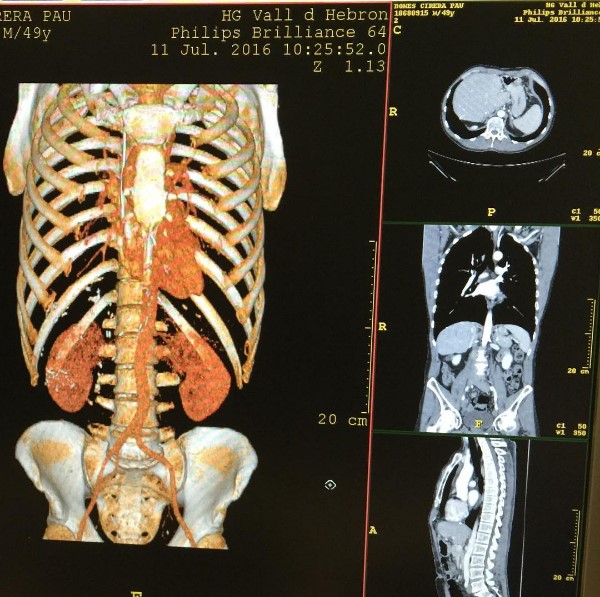

[dropcap]E[/dropcap]l ex vocalista de la agrupación Jarabe de Palo, Pau Donés, anunció hace tres meses que sus exámenes médicos arrojaban que había superado el cáncer de colon que le fue diagnosticado en agosto del año pasado. No obstante, debía someterse a un control 12 semanas después para confirmar que la enfermedad seguía en remisión.